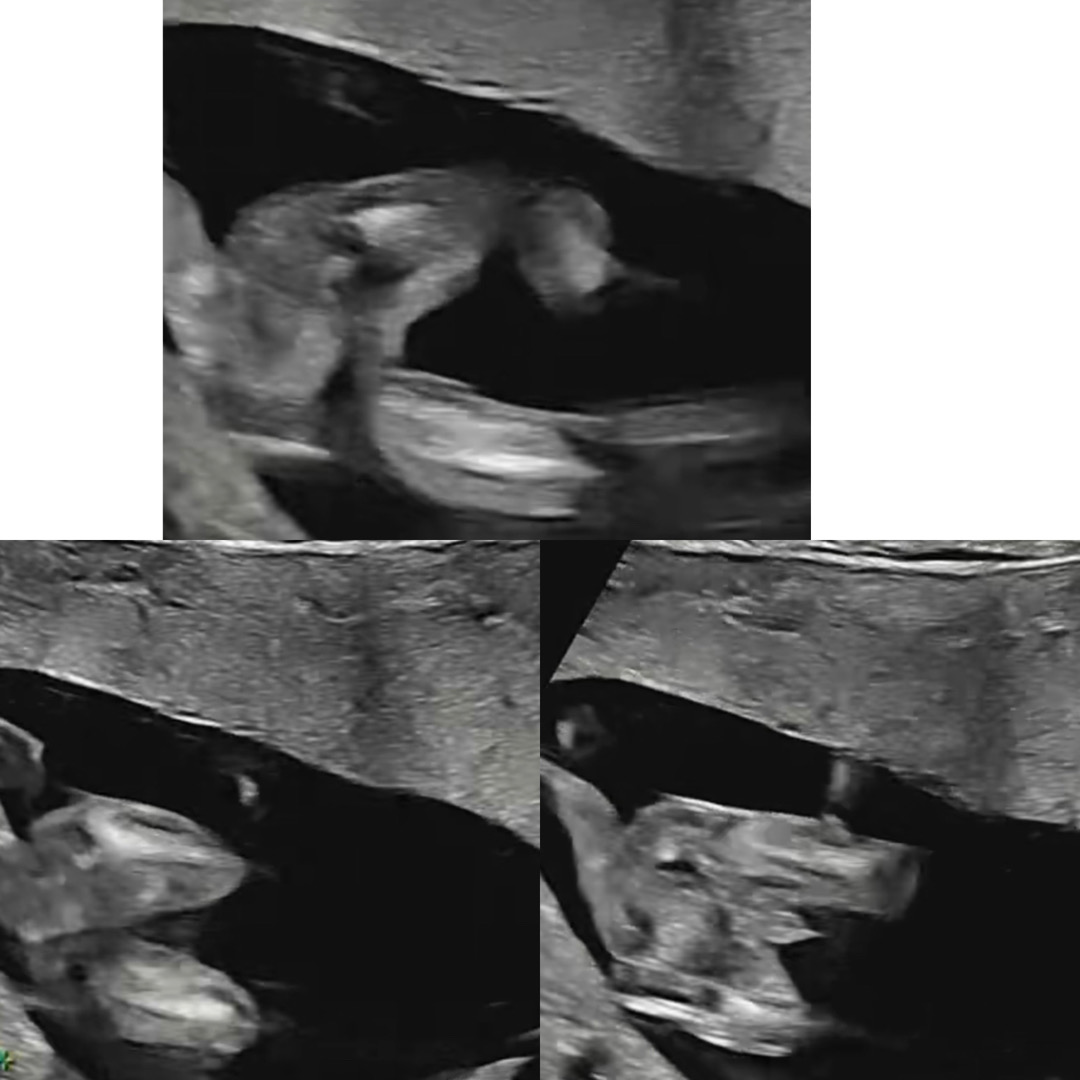

15주차 초음파 성별 같이 봐주세요ㅠㅠ

영상 캡쳐에요 ㅠㅠ 매끈한 각도도 있어서 헷갈리네요… 그래도 보이는게 있으니 빼박일까요?ㅎㅎㅎ

밑에서 오른쬭 보면 아들인데여?! 저두 아들인데..가운데 저 모양 ㅎㅎ..

저요..매끈했는데 아들이였어요 갑자기 다시생겼어요 저렇게ㅠ..ㅋ

아... 맞아요 매끈한데 아들모먼트가 강해서 이럴 수 있나싶어서 긴가민가하고 너무 궁금했어요 ㅠㅠㅋㅋ 확정인가봐요 감사해요!